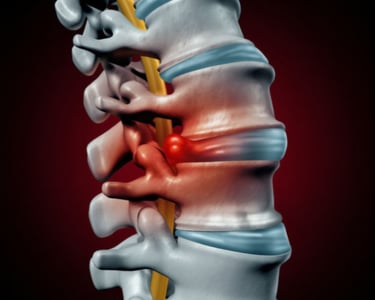

Slipped Disc Surgery

A surgical procedure that removes the herniated portion of a spinal disc that is pressing on nearby nerves. By relieving nerve compression, it alleviates pain, numbness, and weakness in the back, neck, or extremities—restoring mobility and quality of life for patients who have not responded to conservative treatments.